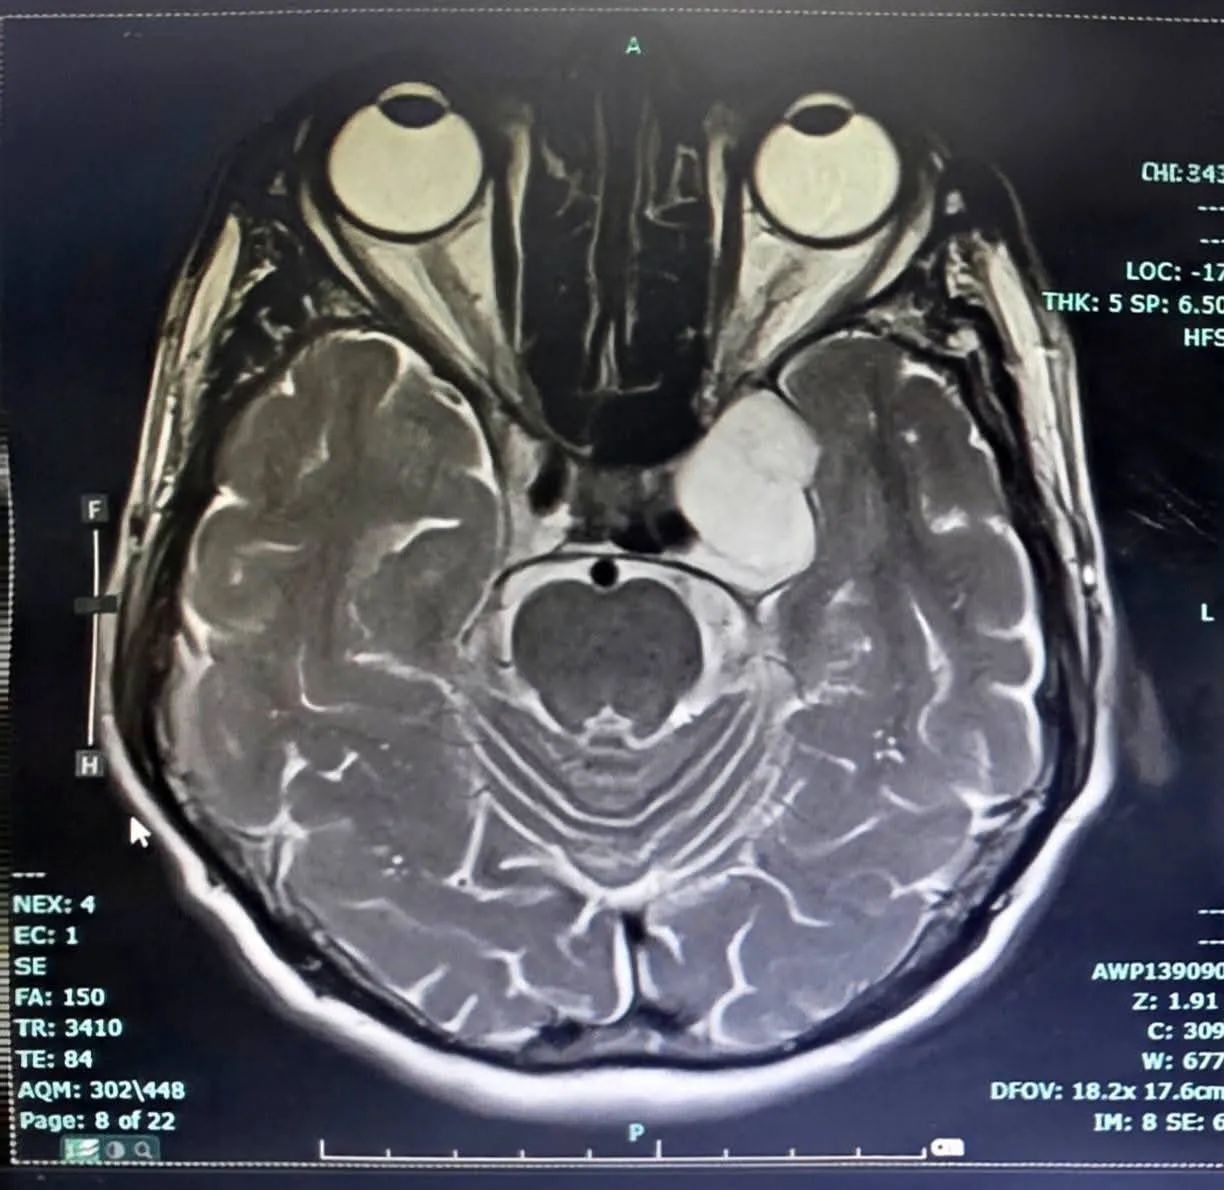

ในวันที่ 24 มีนาคม 2568 โรงพยาบาลลำปางประสบความสำเร็จในการผ่าตัดเนื้องอกฐานสมอง (Skull Base Surgery) บริเวณโพรงไซนัสคาเวอร์นัส (Cavernous Sinus Tumor) ด้วยเทคนิค Endoscopic Transorbital Approach (ETOA) ซึ่งเป็นการผ่าตัดผ่านกล้องส่องทางเบ้าตา ซึ่งจัดเป็นการผ่าตัดแผลเล็ก (Minimal Invasive Surgery) เป็นเทคโนโลยีศัลยกรรมขั้นสูงที่ช่วยลดการบาดเจ็บต่อสมองและโครงสร้างสำคัญ เมื่อเทียบกับการผ่าตัดแบบเปิดกะโหลกขนาดใหญ่ และนับได้ว่าเป็นการผ่าตัด ETOA เพื่อผ่าตัดเนื้องอกสมอง สำเร็จเป็นเคสแรกของเขตสุขภาพที่ 1 กระทรวงสาธารณสุข

การผ่าตัดดำเนินการโดย นพ.เอื้ออังกูรยิ์ สิทธิมงคล ศัลยแพทย์ระบบประสาท โรงพยาบาลลำปาง การผ่าตัดเป็นไปอย่างราบรื่น สามารถนำก้อนเนื้องอกออกได้สำเร็จ หลังผ่าตัดผู้ป่วยฟื้นตัวดี และสามารถกลับมาใช้ชีวิตประจำวันได้ตามปกติความสำเร็จครั้งนี้สะท้อนถึงศักยภาพของโรงพยาบาลลำปางในฐานะศูนย์ศัลยกรรมระบบประสาทขั้นสูง ที่สามารถให้บริการรักษาโรคซับซ้อนในระดับมาตรฐานประเทศ